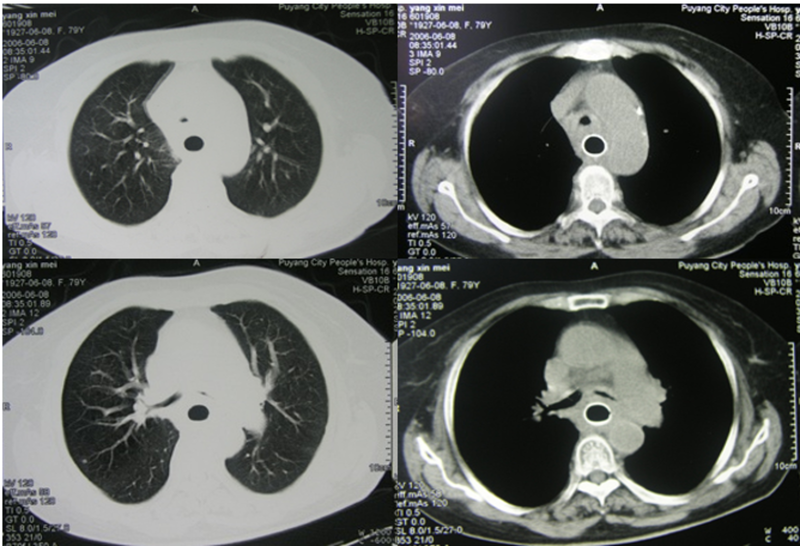

女,79岁,4个月前因食管中上段鳞癌性狭窄行食管内支架置入,能够顺利进食。20天前出现咳嗽、呼吸困难,渐渐加重,夜间不能平卧。4天前胸部SCT示:气管下段及左主支气管严重狭窄(图1)。食管支架推移肿瘤压迫双侧支气管,导致通气困难。取出食管支架前功尽弃,遂引入气道Y型支架解除气道压迫症状(图2)。CT复查主气管和支气管、食管均通畅(图3)